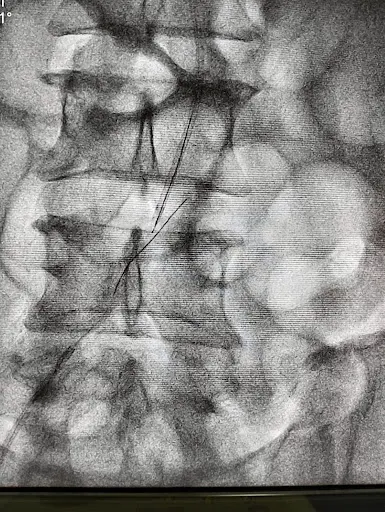

ग्वालियर। चिकित्सा मामलों में नित नई बीमारियां चुनौती बन रही हैं तो दूसरी तरफ हमारे भारतीय डॉक्टर भी उतनी ही तेजी से इन बीमारियों के निदान की तरफ अग्रसर हैं। बीते रोज ग्वालियर संभाग के ख्यातिनाम कार्डियोलोजिस्ट विशेषज्ञ डॉक्टर आशीष चौहान ने एक सफल एंजियोप्लास्टी की हैं। (देखिए वीडियो)

उन्होंने दाहिने सीआईए के पूर्ण अवरोधन के साथ गंभीर अंग इस्किमिया के मामले में

उन्होंने दाहिने सीआईए के पूर्ण अवरोधन के साथ गंभीर अंग इस्किमिया के मामले में

अच्छे एंटे ग्रेड फ्लो के साथ सफल एंजियोप्लास्टी की। इस तरह ये सफलता अंग बचाओ कार्यक्रम में एक और बड़ी उपलब्धि है। बता दें की क्रिटिकल लिम्ब इस्किमिया (सीएलआई) निचले छोरों की धमनियों में एक गंभीर रुकावट है, जो रक्त-प्रवाह को स्पष्ट रूप से कम कर देता है। यह परिधीय धमनी रोग या पीएडी का एक गंभीर रूप है। अगर आपके दिल को धड़कने में कोई परेशानी हो तो बिना देर किए ग्वालियर के ख्याति नाम डॉक्टर आशीष चौहान से संपर्क कीजिए।